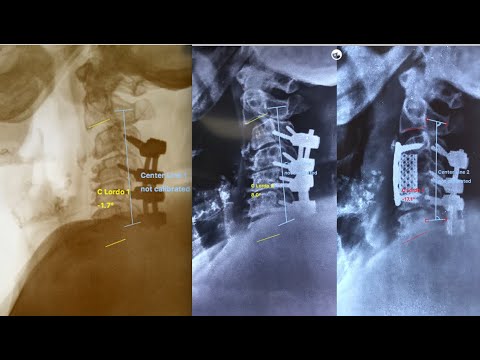

Part 3- Step by step of cervical corpectomy in full HD- Cervical decompression & fixation

Video is part of video series to demonstrate steps of cervical corpectomy for cervical myelopathy. This video is part three of the series showing C4 corpectomy . Video demonstrated important steps of corpectomy and fixation. Part one(https://www.youtube.com/watch?v=izXB7... covered anterior approach to cervical spine and in part two we have seen how to perform a cervical discectomy(https://www.youtube.com/watch?v=1oj_4...).